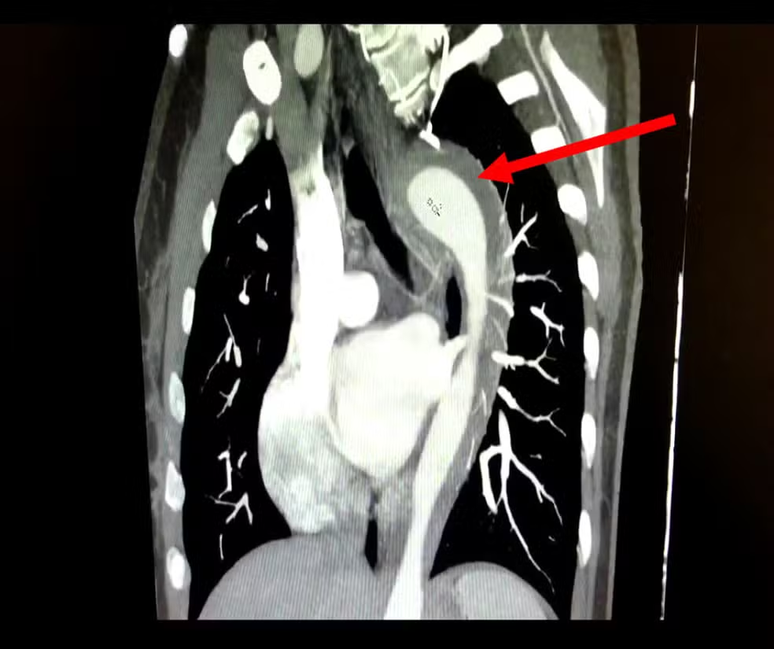

Exames revelaram um hematoma intramural na aorta — sangramento na parede da artéria, condição grave que pode levar a rupturas fatais se não tratada.